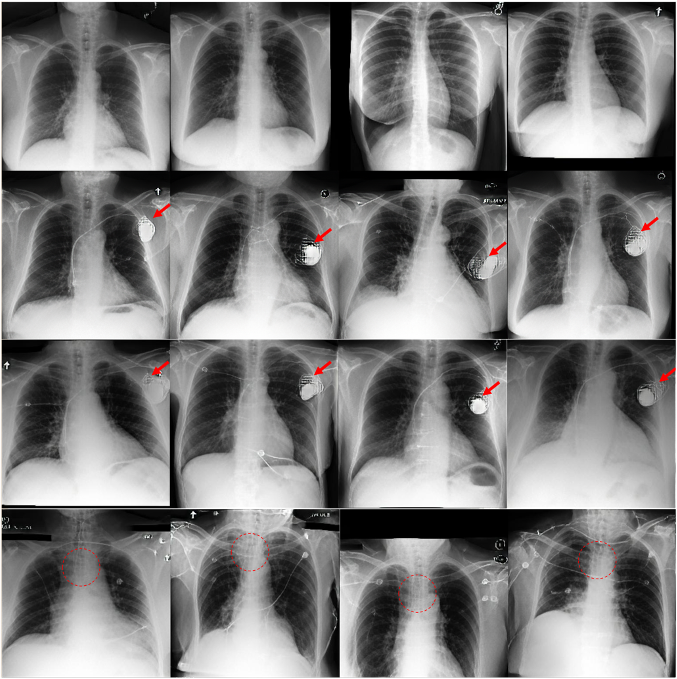

LLM-CXR: Instruction-Finetuned LLM for CXR Image Understanding and Generation

Suhyeon Lee, Won Jun Kim, Jinho Chang, Jong Chul Ye

ICLR, 2024

Leveraging an LLM's language-based reasoning ability for multimodal alignment using a pretrained LLM and image tokenization with a VQ-GAN.